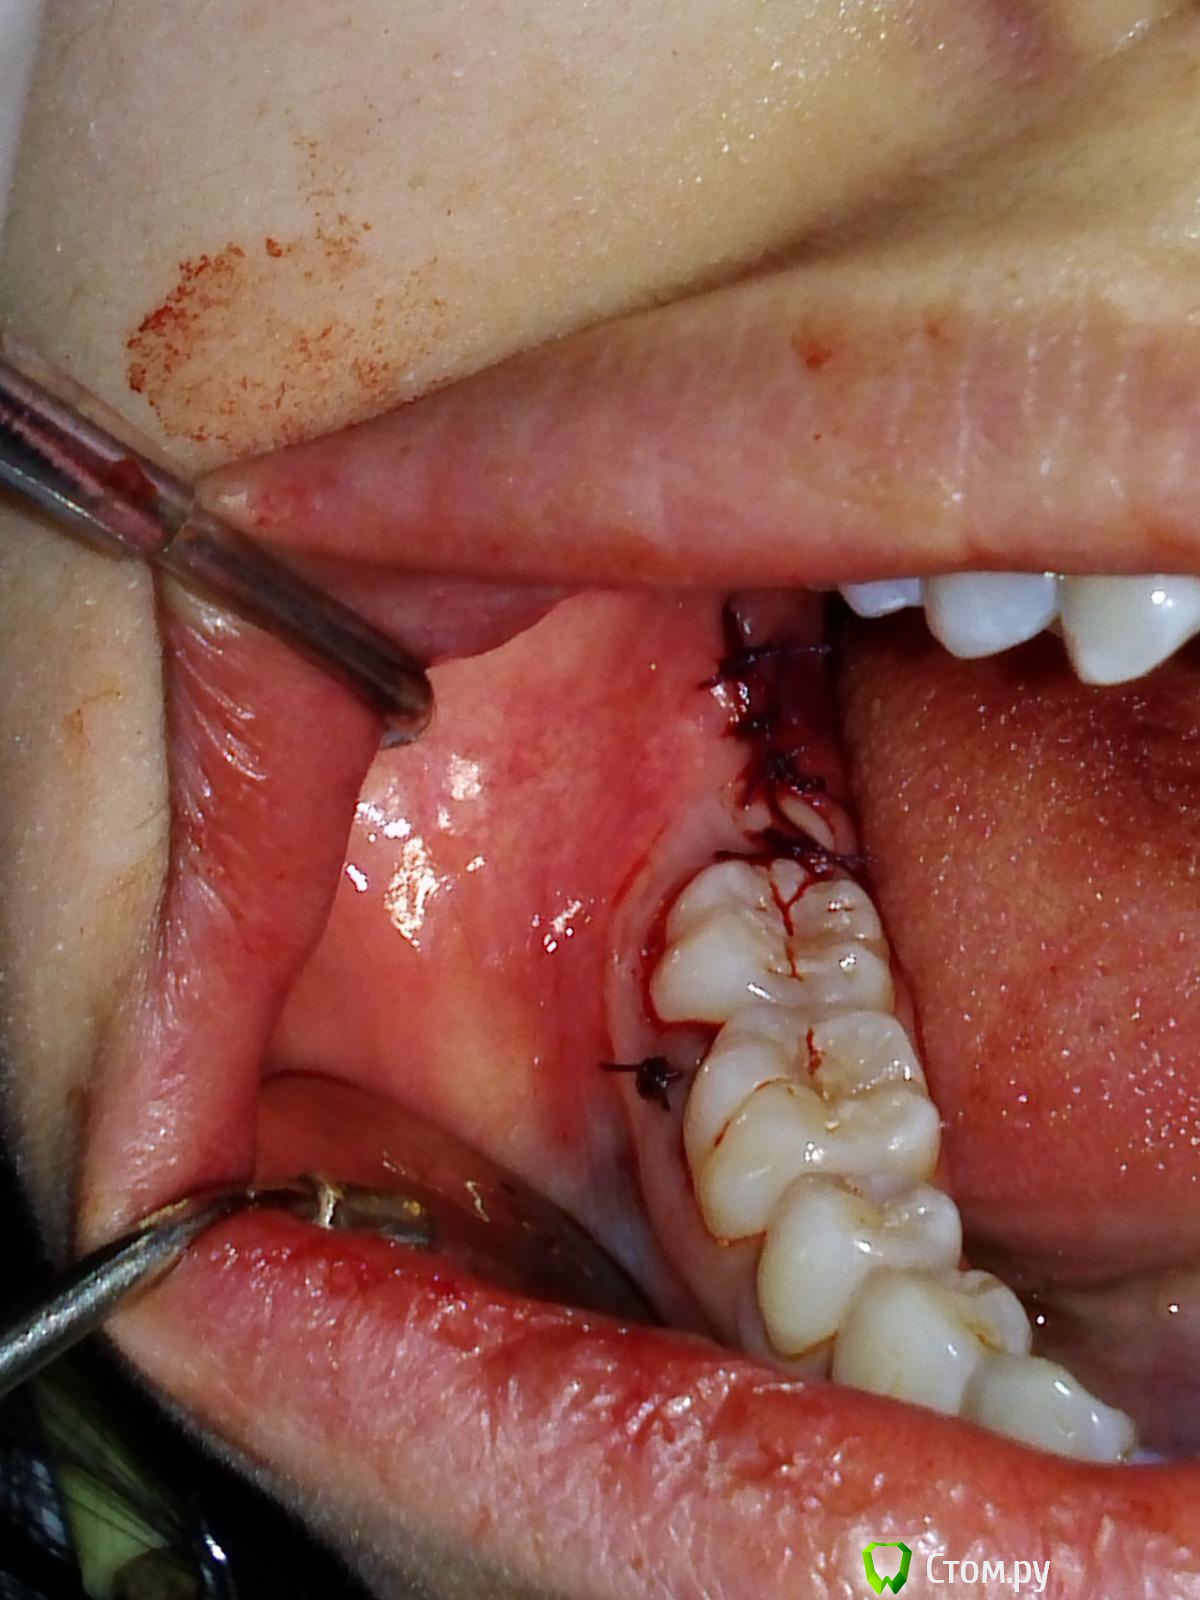

Troy Опубликовано 26 декабря, 2013 Поделиться Опубликовано 26 декабря, 2013 Ретенция, попросил ортодонт 2 Ссылка на комментарий

IvanK Опубликовано 26 декабря, 2013 Автор Поделиться Опубликовано 26 декабря, 2013 Имхо. Можно меньше отслаиваться.Но цель достигнута ) Ссылка на комментарий

Troy Опубликовано 26 декабря, 2013 Поделиться Опубликовано 26 декабря, 2013 Имхо. Можно меньше отслаиваться.Но цель достигнута )Спасибо. Без вертикального разреза меньше не получилось. Ссылка на комментарий

DShu Опубликовано 19 января, 2014 Поделиться Опубликовано 19 января, 2014 Имхо. Можно меньше отслаиваться.Но цель достигнута )А мне такая отслойка больше нравится, чем с вертикальным разрезом. Шить проще, отек меньше. Ссылка на комментарий

kriokov Опубликовано 19 января, 2014 Поделиться Опубликовано 19 января, 2014 А мне такая отслойка больше нравится, чем с вертикальным разрезом. Шить проще, отек меньше.аналогично Ссылка на комментарий

IvanK Опубликовано 20 января, 2014 Автор Поделиться Опубликовано 20 января, 2014 Думаете из-за одного вертикального разреза отек меньше будет?отек из-за отслойки 2 Ссылка на комментарий